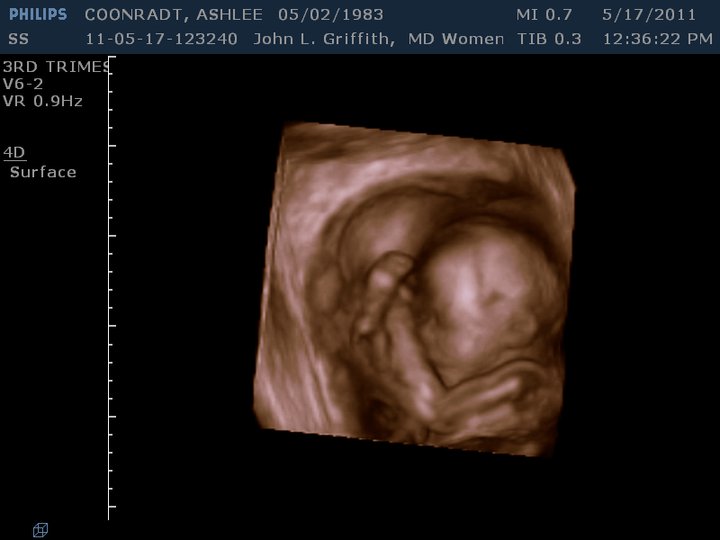

Just thought I would post a picture of the 3D ultrasound my good friend/professional sonographer, Shauna, did of #3! I think this turned out sooooooo good and love how you can already see what a looker she will be! I especially LOVE the crossed little feet up by her face!

Not only was it exciting to see her starting to look like a real baby (and not so much like an alien life-form), but we were also soooooooooo relieved to have this ultrasound go better than the last one...When we went in for the *big* ultrasound, we were devastated to find out that the placenta previa I had with Lu was back again. It wasn't as complete as it was last time, but I was really worried about the complications it might cause as I felt we were

really blessed last time with Lu where everything turned out okay and really without any big problems--minus the 2 months of bedrest... And as if that wasn't enought, another we discovered another bombshell that visit--there was something in the baby's bowels that didn't look good. They weren't really sure what it was, but it could have been a marker for Down's Syndrome or cystic fibrosis among other things. At the very least, unless it went away, they were pretty sure she would have some sort of bowel blockage and would possibly need surgery. Needless to say, we were pretty depressed when we left the doctor's office. My doctor wanted me to come back in a month for another followup ultrasound in hopes that something would have changed by then. In the meantime, my wonderful friend Shauna and my doctor did a lot of checking up on me and talking with other neonatalogists on what we would be in for if things were still the same on the next ultrasound. We kept this on the "down-low" as there was a chance that things would change and I didn't want everyone (especially Great Grandma Barbara) to worry for a month if it would turn out things were fine.

FINALLY the month went by (longest of my life)and I was able to go in for my ultrasound. I was telling Coby the night before that even if just one thing was gone, I think I'd be able to handle it much better and when I went in the next day, it was such a

miracle because BOTH things had resolved! My placenta had moved

clear up and the spot on the baby's bowel was

completely gone! I feel like we have been soooooo blessed again! I love my family and love this little girl so much already! I am so relieved that things are looking so much better!